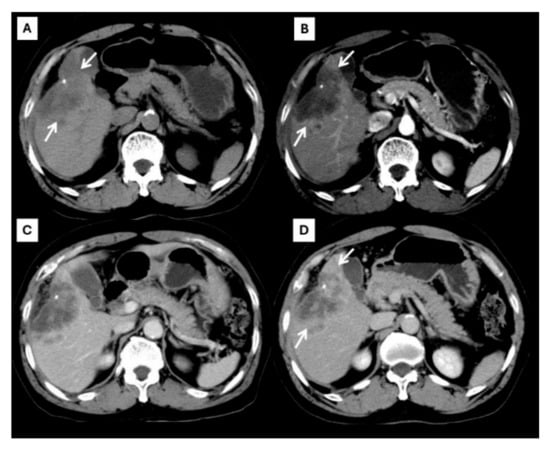

| Later arterial phase | Arterial phase hyperenhancement | Rim-like enhancement |

| Portavenous phase | Non-peripheral washout | Progressive peripheral enhancement |

| Delayed phase | Capsule enhancement | Progressive peripheral enhancement |